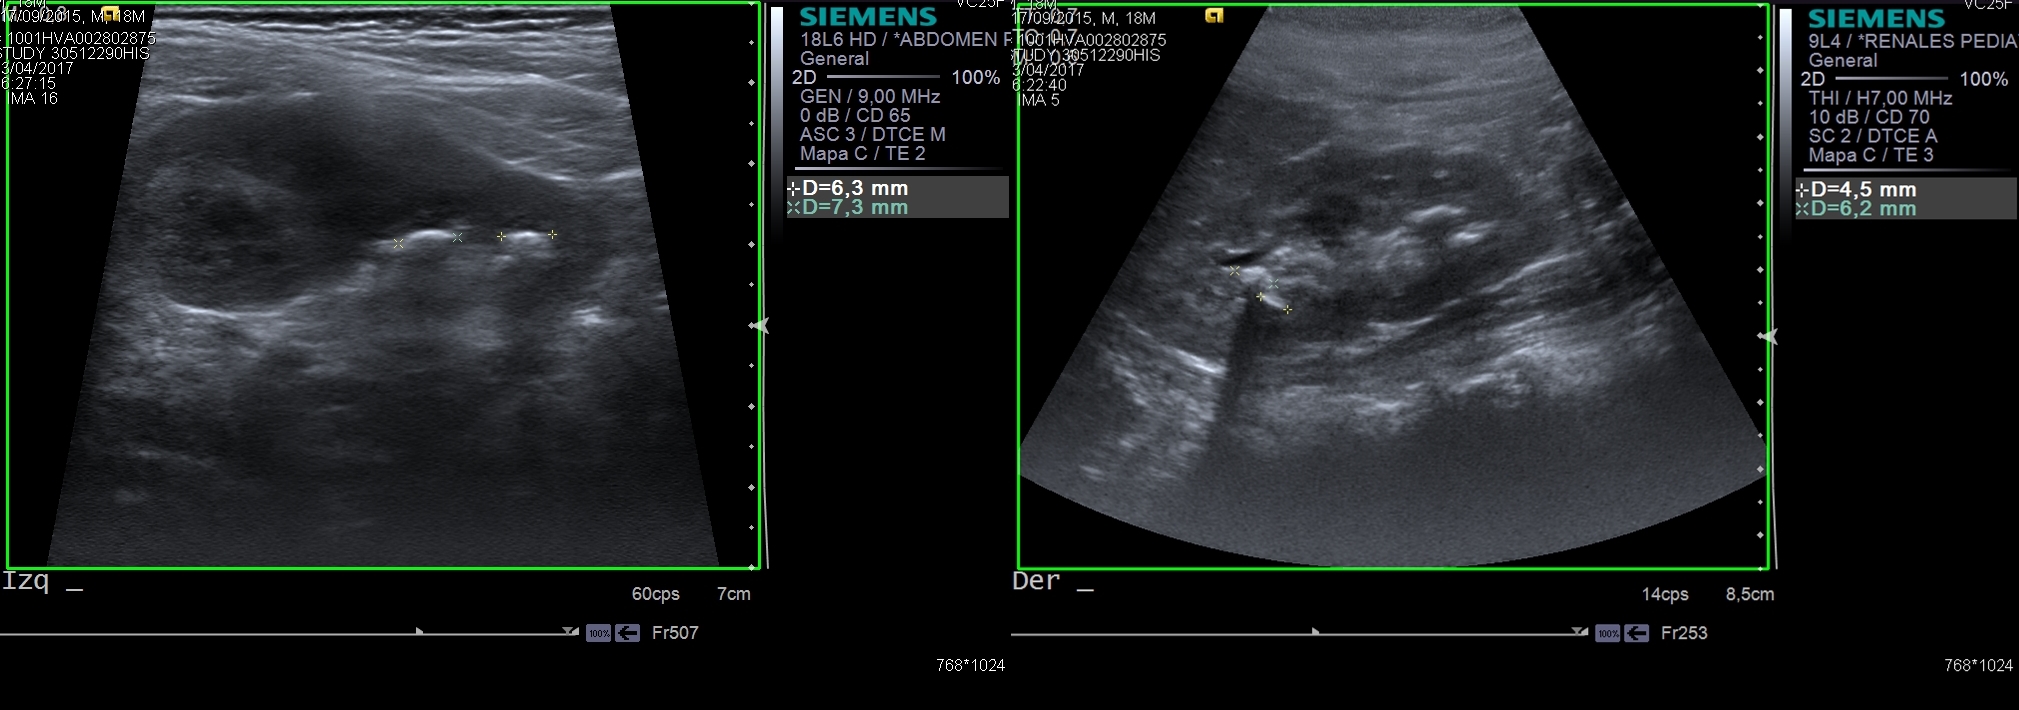

Cuando estamos ante un paciente de pediatría, la ecografía será siempre la técnica de elección en primer lugar. Pues se trata de una técnica no invasiva, que no irradia al paciente. Esta permite valorar la morfología y tamaño de los órganos, y la presencia de cualquier tipo de masa o quiste. Como según lo que refiere la madre el paciente presenta una clínica tan inespecífica, se estudiarían todos los órganos abdominales para descartar la patología en cada uno de ellos.

Haz click en las imágenes para verlas ampliadas